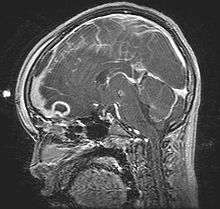

Pott's puffy tumor, first described by Sir Percivall Pott in 1760, is a rare clinical entity characterized by subperiosteal abscess associated with osteomyelitis. It is characterized by an osteomyelitis of the frontal bone, either direct or through haematogenic spread. This results in a swelling on the forehead, hence the name. The infection can also spread inwards, leading to an intracranial abscess. Pott's puffy tumor can be associated with cortical vein thrombosis, epidural abscess, subdural empyema, and brain abscess. The cause of vein thrombosis is explained by venous drainage of the frontal sinus, which occurs through diploic veins, which communicate with the dural venous plexus; septic thrombi can potentially evolve from foci within the frontal sinus and propagate through this venous system. This type of chronic osteomyelitis of the frontal bone is confused with acute sub-periosteal abscess of the frontal bone, which presents as a discrete collection over the frontal sinus.

Although it can affect all ages, it is mostly found among teenagers and adolescents. It is usually seen as a complication of frontal sinusitis or trauma.